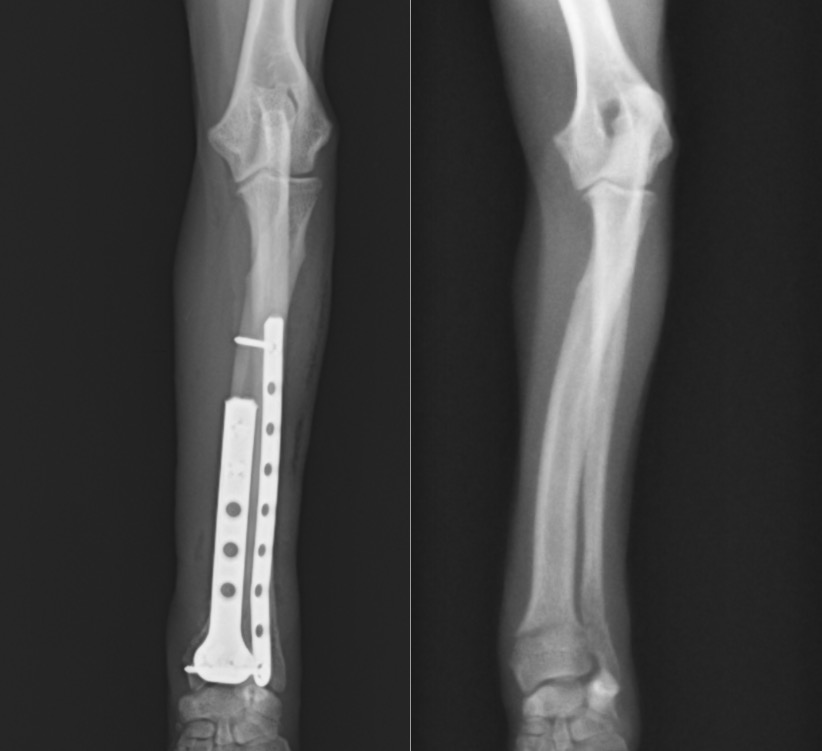

手術はダブルプレート法で行いました。

正面に1.5㎜コンディラープレート、側面に1.1mmストレートプレートを設置し、

結果的には手首の関節に近い小さい骨片にも3本のスクリューを挿入することができました。

術後の経過は良好であり、退院する頃には手術をした足も問題なく使って歩いてくれていました。